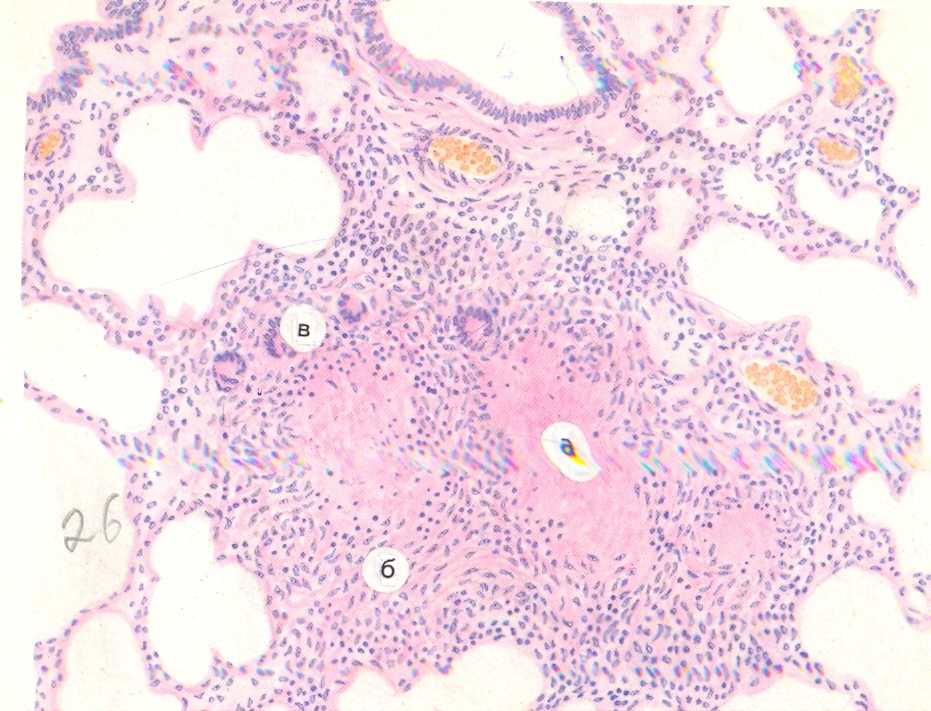

Микроскопический взгляд на мишитарный туберкулез легкого: фотодокументация

Раздел: Снимки-откровения